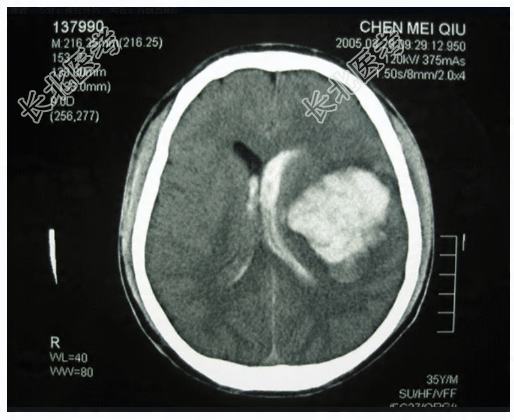

- 多项选择题1.提示:CT片,见下图。可得出的诊断有

A、左侧颞叶脑挫裂伤

B、脑室内出血

C、左侧颞叶脑内血肿

D、左侧颞叶胶质瘤

E、弥漫性脑水肿

F、胶质母细胞瘤